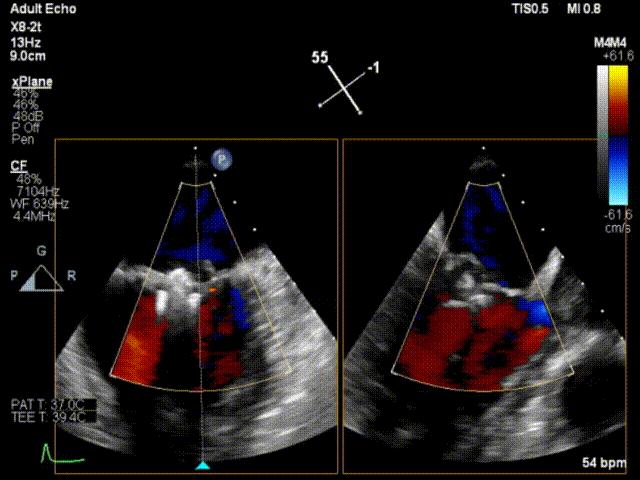

患者男性,63岁,主诉间歇性心悸5年,加重3月。门诊以“二尖瓣关闭不全”收入西京医院。术前超声提示:二尖瓣关闭不全,前叶26mm,后叶22mm,二尖瓣腱索断裂,后叶P1区及部分P2区脱垂,脱垂高度9mm,脱垂宽度15mm,舒张期瓣口面积约6.8cm²,反流束位置位于1区偏2区,Carpentier分型Ⅱ型,心功能Ⅳ级(NYHA分级)。

术前超声心动图